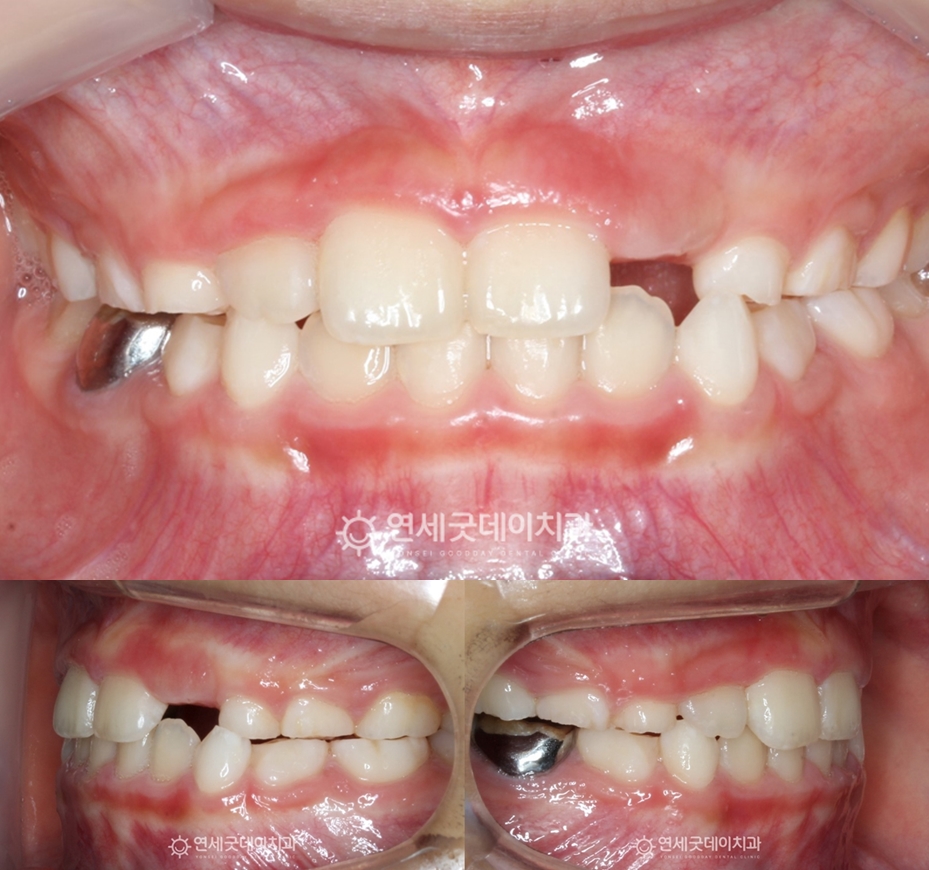

▲ 치료전 안모 (촬영시기 : 2024년 9월)

아랫니가 거꾸로 깊게 물리는 심한 반대교합으로

프리올소는 치아 배열뿐 아니라 턱 성장 방향을 유도해 올바른 얼굴 균형을 잡아주고,